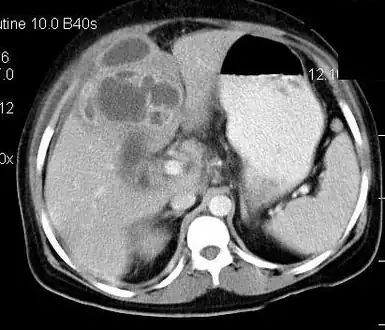

Gallbladder

Contrast enhanced computed tomography of the abdomen is showing gall bladder empyema with perforation and formation of liver abscess.